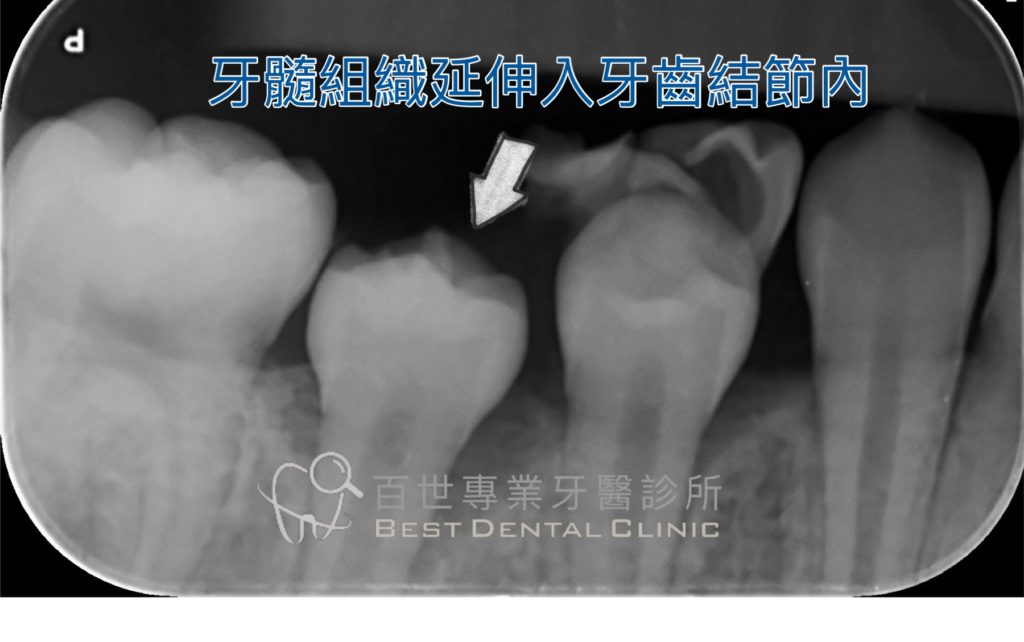

這個突起並非單純的琺瑯質,而是由琺瑯質、牙本質,甚至可能包含牙髓(神經)所組成。

因此,一旦斷裂或磨耗,就可能導致牙髓暴露與牙痛。